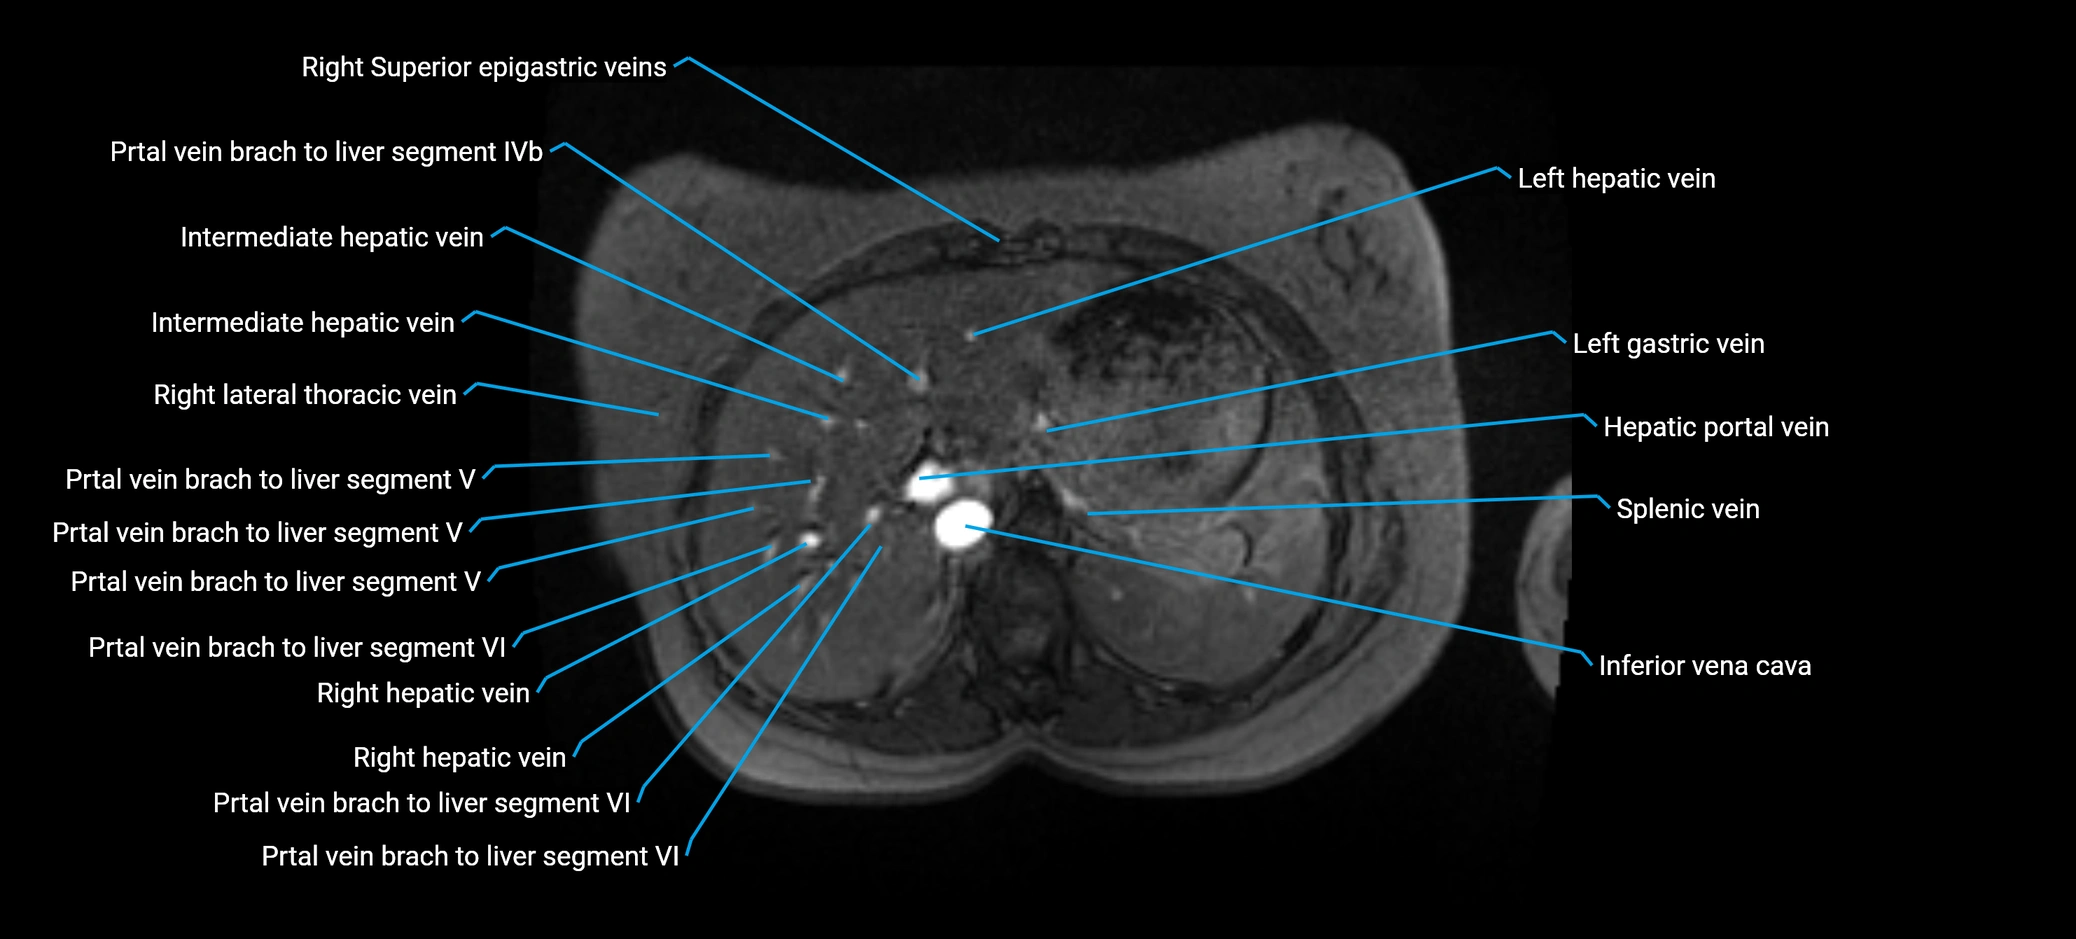

The anterior right branch of the portal vein is a major intrahepatic division of the right portal vein. After the main portal vein bifurcates into right and left branches, the right portal vein divides into anterior and posterior segmental branches.

The anterior right branch supplies the anterolateral liver segments (Segment V) and anteromedial liver segments (Segment VIII) within the right hepatic lobe. It operates as a key vascular route delivering nutrient-rich portal venous blood to the central and superior right liver.

This segmental vasculature is of major importance in hepatic surgery, embolization, segmental resection, transplantation, and imaging-based liver segmentation.

MRV TOF (Time-of-Flight MR Venography):

• Appears as a bright, high-signal vascular channel representing flowing blood

• Clearly shows branching pattern of right portal vein into anterior and posterior branches

• Best in coronal or axial reconstructions for segmental mapping

• No need for contrast, relies on flow-related enhancement

Post-Contrast T1 Fat-Sat GRE:

• Enhances brightly and homogeneously during the portal venous phase

• Clearly delineates branching into segments V and VIII

• Best sequence for evaluating patency, caliber, and anatomic variants

• Early arterial phase: minimal enhancement

• Delayed phase: gradual washout but still brighter than hepatic parenchyma